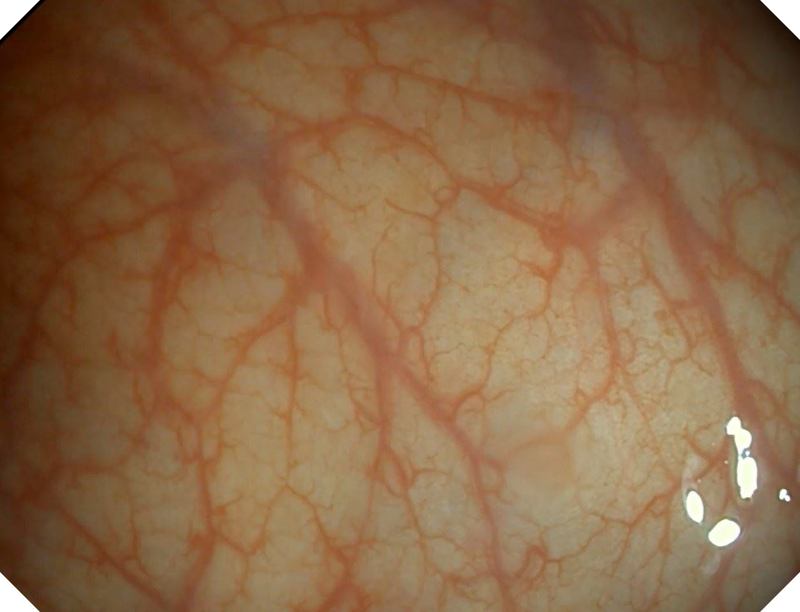

白光图像

白光图像

SFI图像

SFI图像